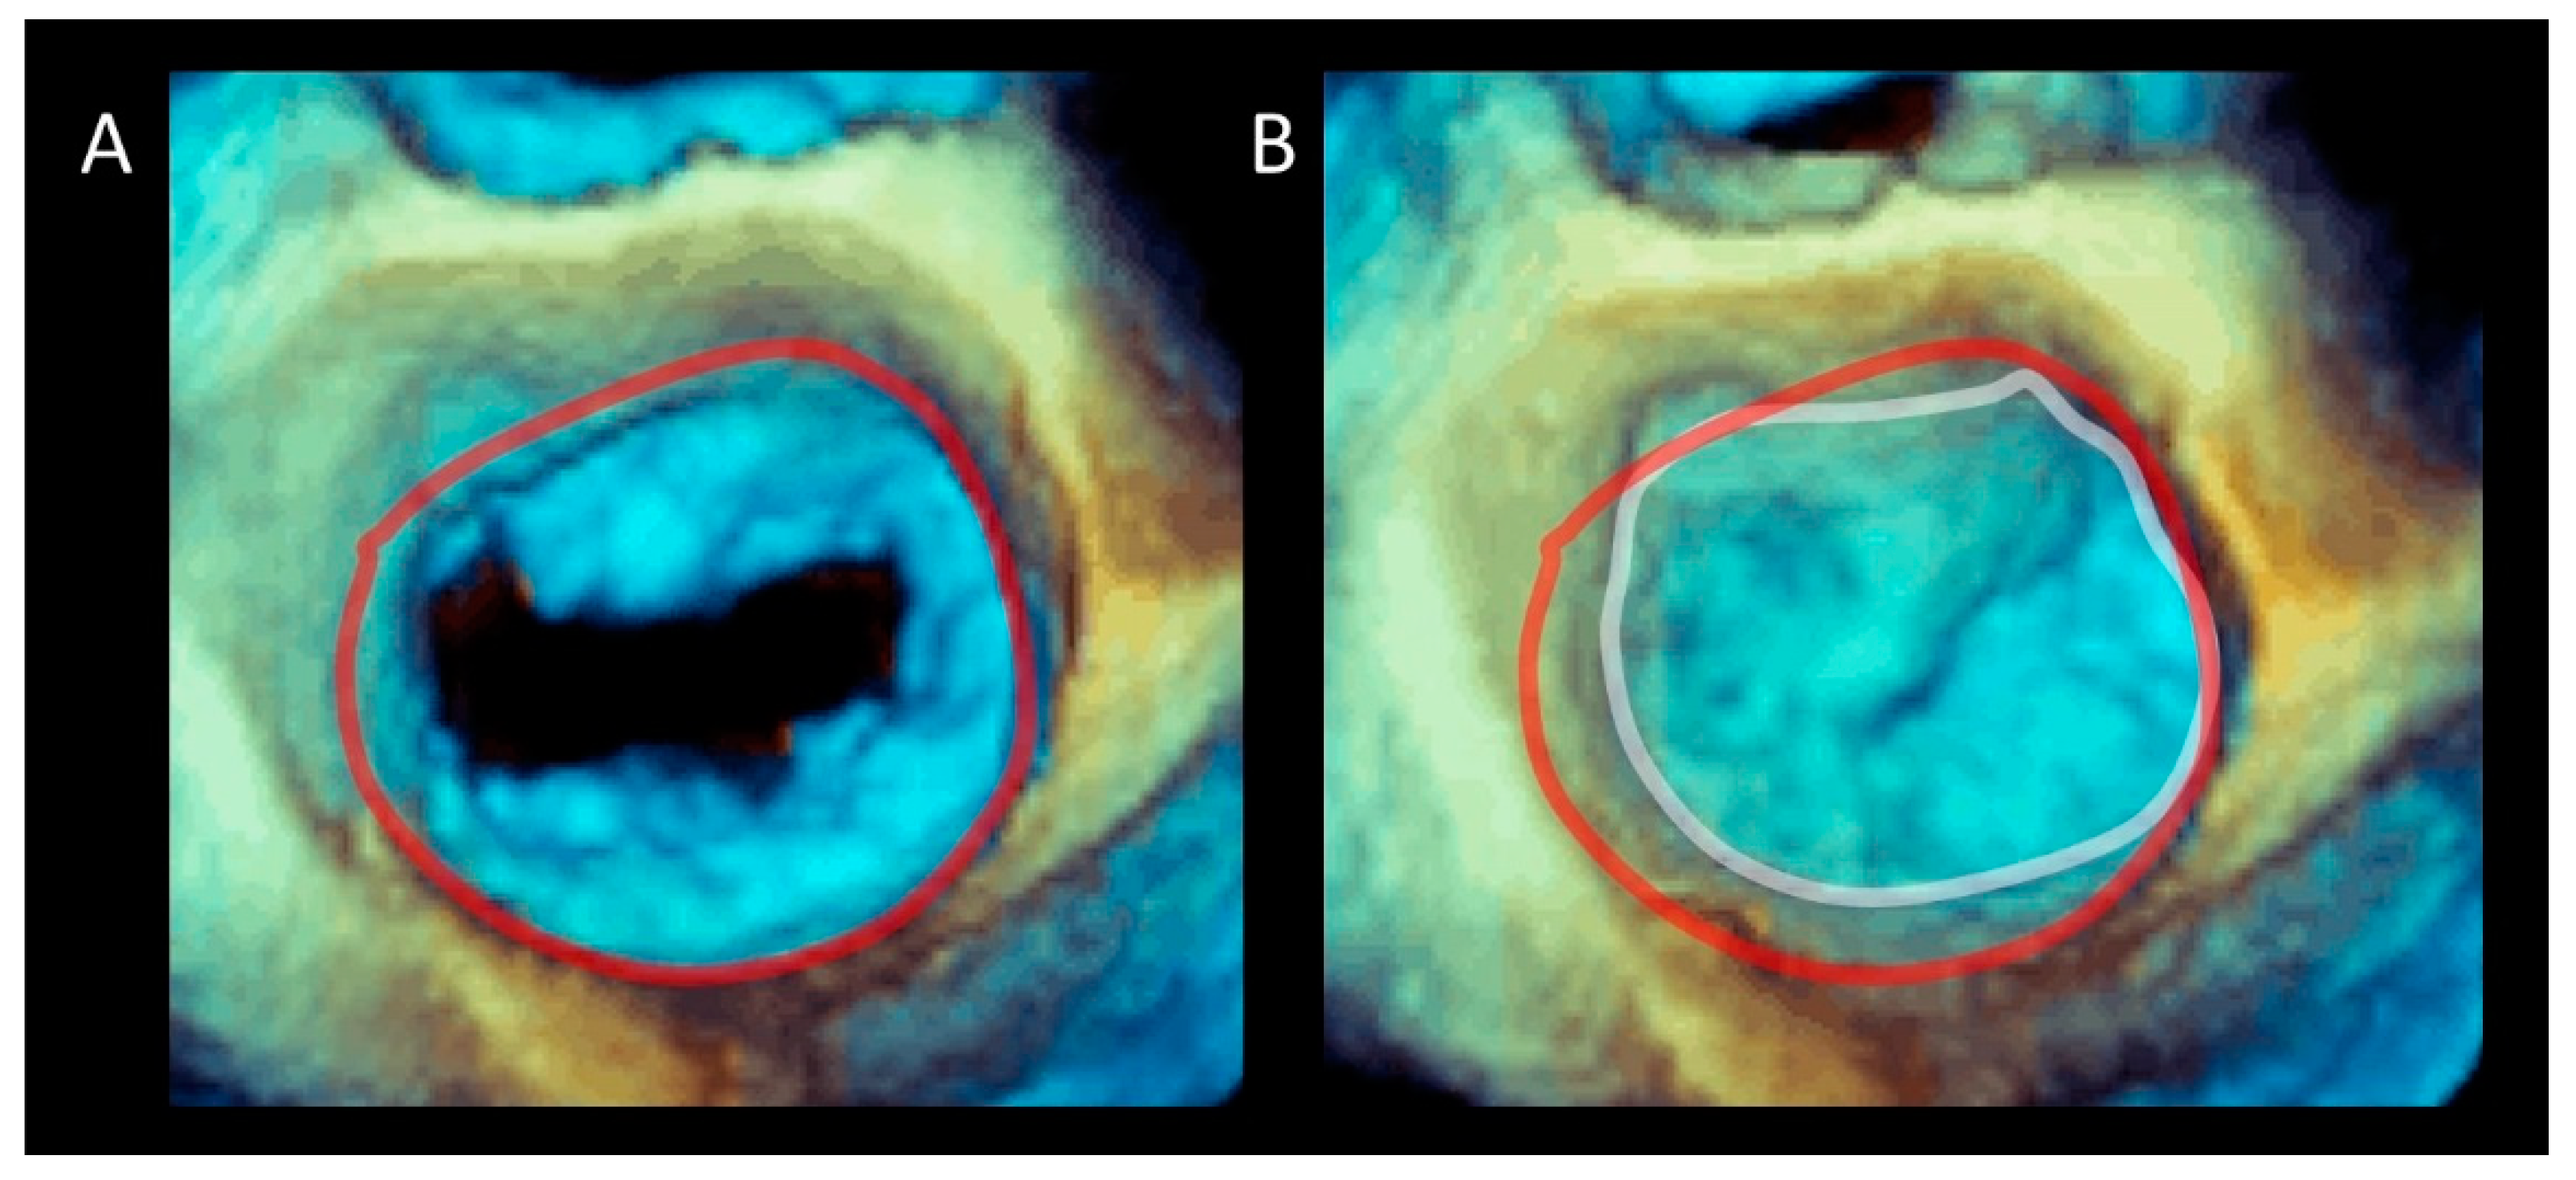

2. Mitral Annulus

Imaging Techniques

6.1.1. Dilation